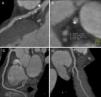

We describe the case of a 47-year-old man with no cardiovascular risk factors or relevant personal or family history, a competitive athlete participating in the Ironman triathlon of long-distance swimming (3.8 km), cycling (180 km) and running (42.2 km). He denied taking any regular medication or substance abuse (tobacco, alcohol or anabolic steroids). Following a respiratory infection, he was referred by his general practitioner for thoracic computed tomography (CT), which showed an incidental finding of “coronary artery calcification”. He was accordingly referred for cardiac CT to quantify the extent of coronary calcification and to exclude obstructive coronary artery disease (CAD). His calcium score was 226, with involvement of all the epicardial coronary arteries, but particularly in the proximal anterior descending artery (Figure 1). According to published normograms,1 this figure is well above that expected for a man of his age (above the 90th percentile), and in the expected range (50th percentile) for someone in the sixth decade of life.

Contrast imaging excluded obstructive CAD but revealed mixed plaques, predominantly calcified, throughout the coronary tree, particularly in the left main and the proximal segment of the anterior descending artery. Positive remodeling was evident in some plaques (Figures 2 and 3).